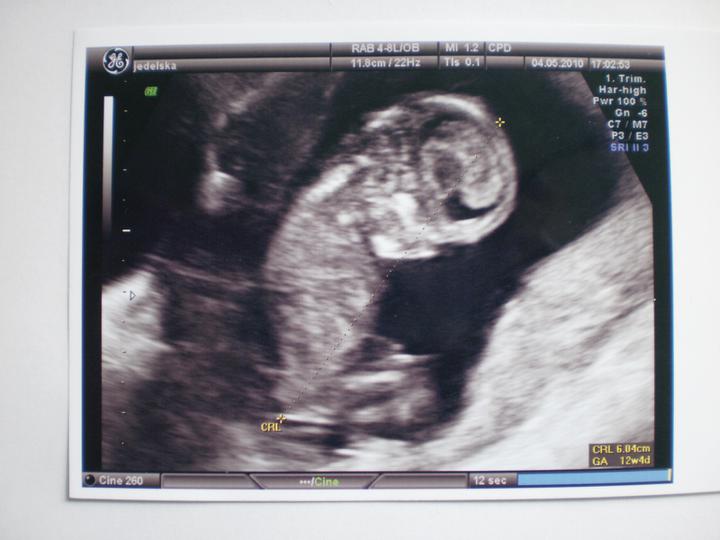

14+4...vyšetření u pana doktora taky v pohodě :o)